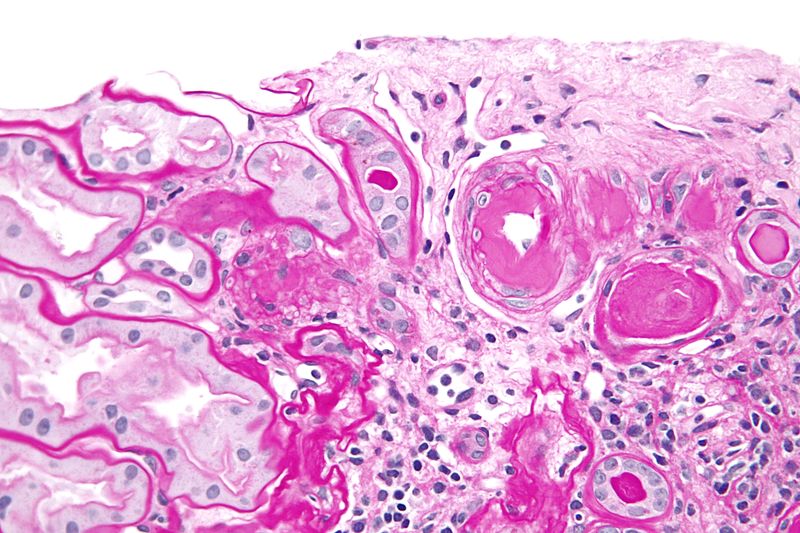

Histologically, atherosclerosis consists of a fibromuscular cap covering a necrotic lipid core (mainly cholesterol).

Atherosclerosis is initialized as fatty streaks (flat yellow lesions of the intima consisting of lipid-laden macrophages).

The fatty streaks tend to presents early in life for the majority of teenagers.